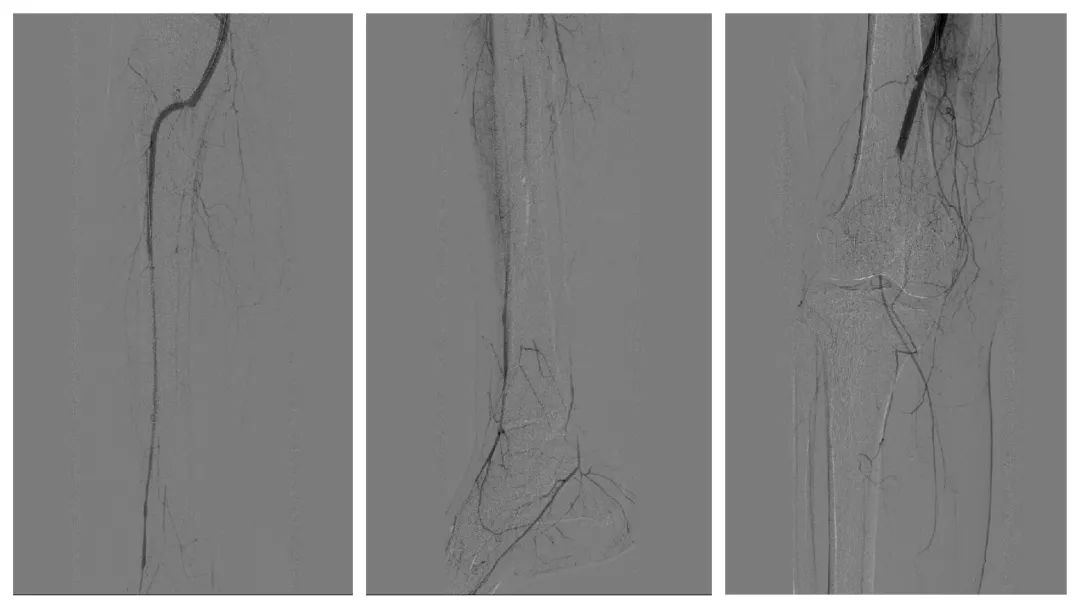

术中,困难重重,险象环生。常规全肢或中央型下肢深静脉血栓治疗,是经健侧大腿股总静脉穿刺,放置下腔静脉滤器,预防致死性肺栓塞,再外周抗凝溶栓或静脉穿刺抽吸血栓治疗。但是患者双侧股总、左侧髂静脉血栓,需要经右颈内静脉穿刺手术。病人左侧偏瘫失语,不能配合,颈内静脉穿刺有误伤颈动脉及血、气胸风险。考虑到患者仅左腿高度肿胀,刘主任决定先行右下肢静脉造影,观察右股静脉血栓情况,如位置不高或血栓不多,可经右腿股总静脉穿刺放滤器,避免发生肺栓塞猝死。

造影发现右股总静脉有附壁血栓,如施行常规右大腿根部股总静脉穿刺放滤器,有血栓被推走,患者在手术台上极有可能出现肺栓塞风险。病人同时患有右腘动脉栓塞也必须尽快取出。一条腿,动、静脉同时有血栓,上下位置还不同,这个病例的确给专家们出了一道难题。如果施行在高位穿刺髂外静脉,会因术后无法压迫,引起大出血,失血性休克;如果向下右腿股浅静脉穿刺放滤器,会因局部还要切开动脉取栓,无法压迫止血。刘洪主任凭借丰富的临床经验,决定同期手术“一口两用”。从右腿根部纵行切开,同时暴露股浅动、静脉。先经右股浅静脉小心向上穿刺,放滤器阻止血栓上行至肺部,避免发生致死性肺栓塞,并迅速缝合静脉;再向下穿刺右股浅动脉造影,用导丝双腔取栓导管反复多次操作,取出长度达15厘米,形状宛如一条“血蛇”的暗红色陈旧血栓。手术历时近4小时,术后肢体温度恢复,安返病房。